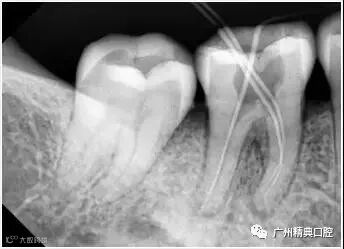

6、根管充填

封闭整个根管系统、堵塞主根管和侧副根管出口、防止微生物和液体的渗漏。无论是侧方加压法还是垂直加压法,应做到根管充填致密,根管充填后X线片上无根管腔隙,也不能超出根尖孔。